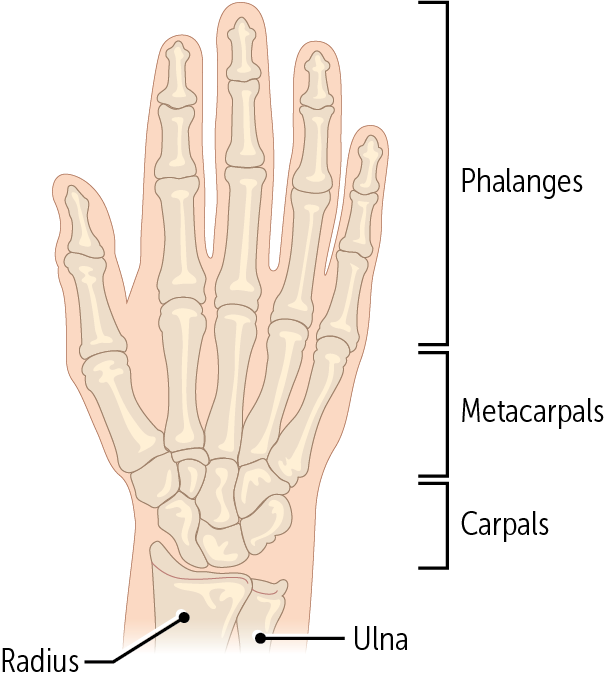

The hand comprises__ bones: __ carpal bones, __ metacarpal, and __ phalangeal bones

27, 8, 5, 14

Every digit is made up of a metacarpal bone and three phalanges, except for the ___________, which only has two phalanges.

thumb (aka the pollux - Latin for thumb)

The metacarpals are the most proximal bones of the digits (Figure 14). These bones—numbered 1 through 5, with 1 being the _____—connect the carpals to the proximal phalanges

thumb

________ are the longest bones in the hands. They have a base, body, and head; like the ulna, their head is distal and their base is proximal.

The metacarpals

Every finger has three phalanges (proximal, medial, and distal) except for the _____, which only has two (the proximal and distal).

thumb